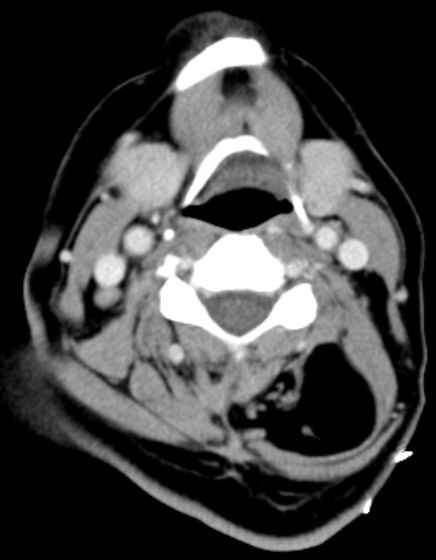

67-jährige Patientin mit einer Raumforderung im Nacken. Das CT zeigt eine fettdichte Struktur innerhalb der dorsalen Halsmuskulatur.